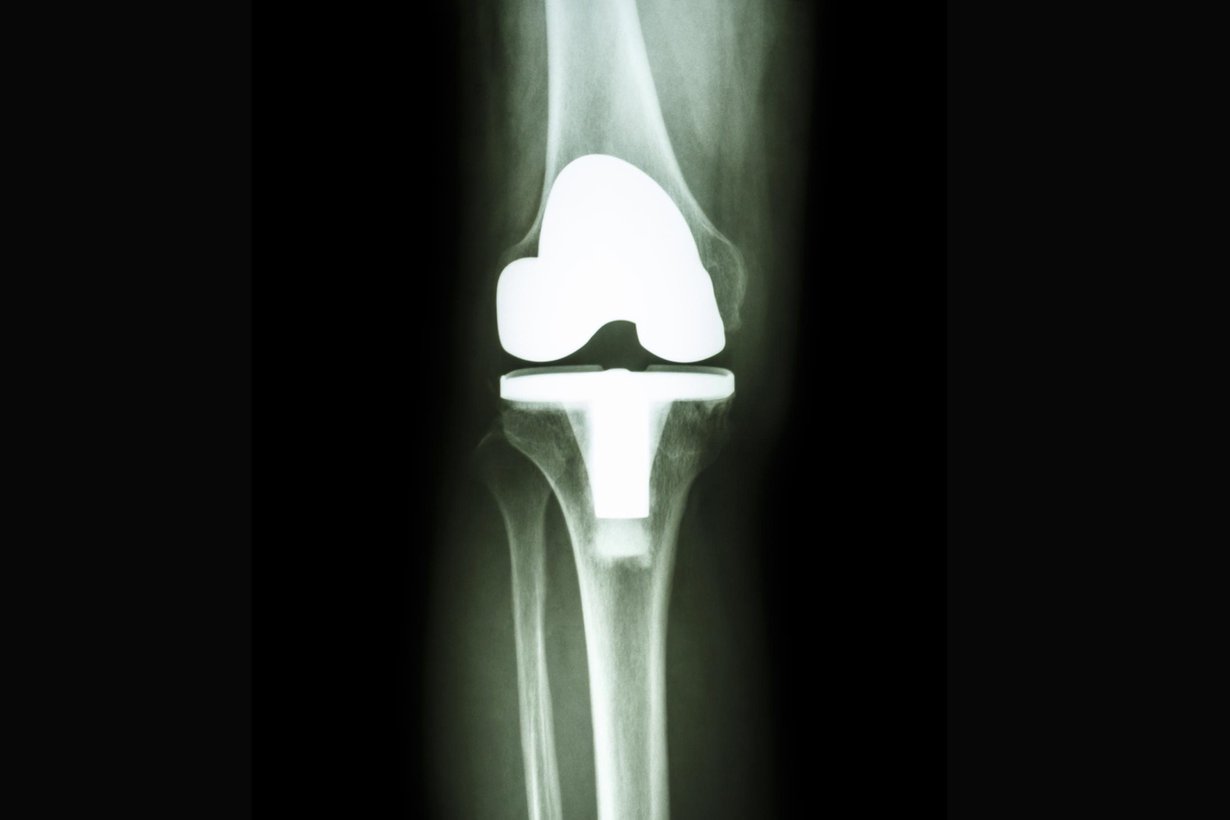

Haluaisitko polven tekonivelleikkaukseen? Lue asiantuntijan vinkit

Polven tekonivelleikkaus sujuu sitä varmemmin, mitä rutinoituneempia sairaala ja leikkaava lääkäri ovat, sanoo Terveystalon ortopedi, liikuntatieteen erikoislääkäri Tapio Kallio.

• Polven tekonivelleikkaus parantaa elämänlaatua vähintään 15 vuoden ajaksi.